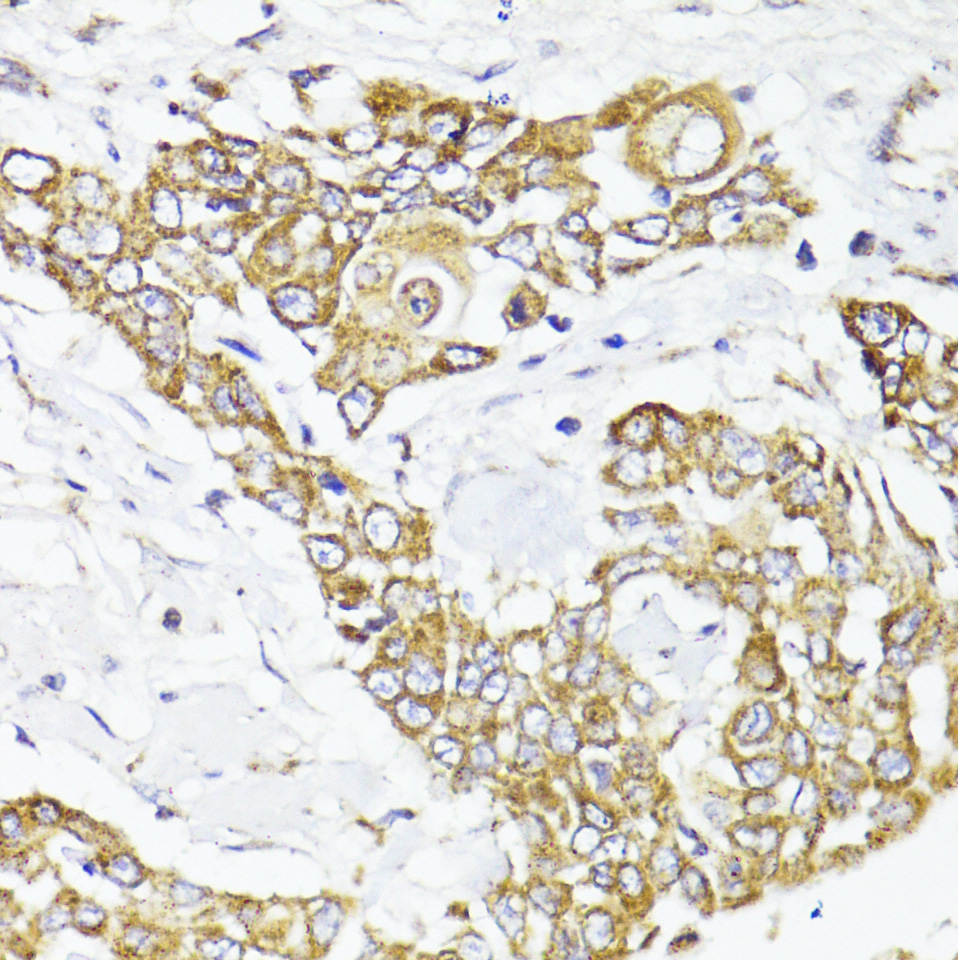

Immunohistochemistry of paraffin-embedded human colon carcinoma using MAVS antibody.